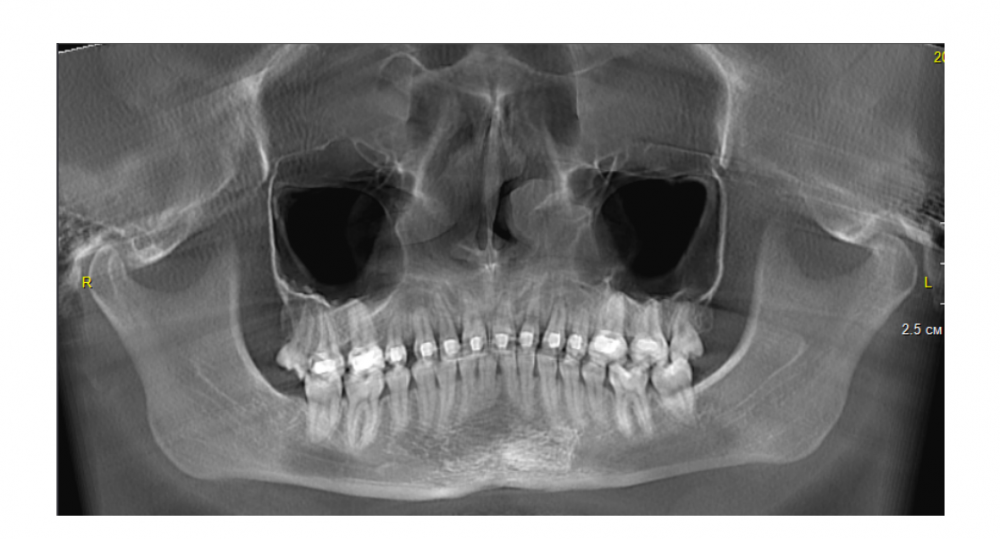

Loya Опубликовано 10 июля, 2023 Поделиться Опубликовано 10 июля, 2023 Добрый день! Помогите пожалуйста с таким вопросом. Носила брекеты 5 лет, в процессе лечения были удалены 4ки и активно двигались 2-ки и 3-ки под большим натяжением. Незадолго до снятия делала КЛКТ, было подозрение на трещину/перелом шейки зуба 2.2, лечащий ортодонт сказала, что скорее всего "засвет", тк не может быть перелома без боли. Консультировалась у двух врачей, один сказал, что видит перелом и зуб нужно удалять. Второй врач сказал, что есть трещина, судя по всему, очень давняя, нужды удалять он не видит. По поводу шатания зубов сказали, что со временем нарастет костная ткань и все будет нормально. Прошло два года после снятия брекетов, двойка (в которой трещина) и соседняя тройка (клык) до сих пор подвижны (шатание 1-2 мм наверное), но нет боли и неприятных ощущений. Снимки в эти 2 года не делала. Хотела узнать, что мне стоит делать, можно ли ходить так дальше, или есть вероятность воспаления (прогресса вроде бы нет), есть ли действительно перелом/трещина и что лучше всего сделать с этой проблемой, пропадет ли подвижность со временем или нужно делать имплантацию? Прикладываю снимок двухлетней давности, не знаю, насколько он актуален спустя 2 года, новый пока не делала Ссылка на комментарий

Irouil Опубликовано 10 июля, 2023 Поделиться Опубликовано 10 июля, 2023 Ритейнеры Вы не носите? На "засвет" и на перелом/трещину не похоже, скорее на резорбцию корня Делайте свежий снимок 1 1 Ссылка на комментарий

Irouil Опубликовано 10 июля, 2023 Поделиться Опубликовано 10 июля, 2023 Лучше сделать КЛКТ Сам факт резорбции в Вашем случае скорее всего на подвижность зуба не влияет, если картина на КЛКТ будет сравнимой с предоставленной я бы рассмотрел возможность шинирования подвижных зубов 1 Ссылка на комментарий